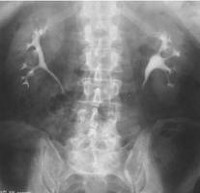

Обзорная урография ребенка предшествует более детальному рентгенологическому обследованию больного с заболеваниями мочевыделительной системы. Обзорная урограмма показывает область от верхних полюсов почек до уретры. Обзорная урография позволяет ребенку оценить топографию, размеры и форму почек, выявить наличие камней в различных отделах мочевыводящих путей, ненормальное развитие мочевыводящих путей, наметить объем и последовательность дальнейшего обследования. Накануне обзорной урографии ребенку назначают безгазовую диету и очистительную клизму.

Обзорная урография ребенка - рентгенологическая техника, которая достигается путем визуализации верхнего и среднего отделов мочевыводящих путей. В детской урологии и нефрологии обзорная урография и УЗИ почек ребенка обычно являются самой первой стадией обследования молодого пациента, что позволяет наметить ход дальнейшей диагностики. Чтобы получить более детальное изображение исследуемой области после обзорной урографии, ребенку можно сделать контрастную экскреторную урографию, цистографию, ретроградную пиелографию, селективную почечную ангиографию, флебографию, компьютерную томографию (МСКТ) почек, МРТ почек, статическую или динамическая сцинтиграфия почек.

XII пара ребер, нижней части позвоночника, таза и почек тени визуализируются в рентгеновских лучах. В норме правая почка находится в 12-м видении грудной клетки - 3 поясничных позвонка (Th12-L3), слева - на уровне 11-го грудного отдела - 2 поясничных позвонка (Th11-L2). Край XII слева пересекает центр почки, а справа - уровень ее верхнего сегмента. Наполненный мочевой пузырь определяется как эллипсоидная формация. Тени почек однородные, контуры ровные. Неизмененные мочеточники не видны при детском урографическом исследовании. Мышцы поясницы определяются как тени в форме усеченной пирамиды, направленные вверх.